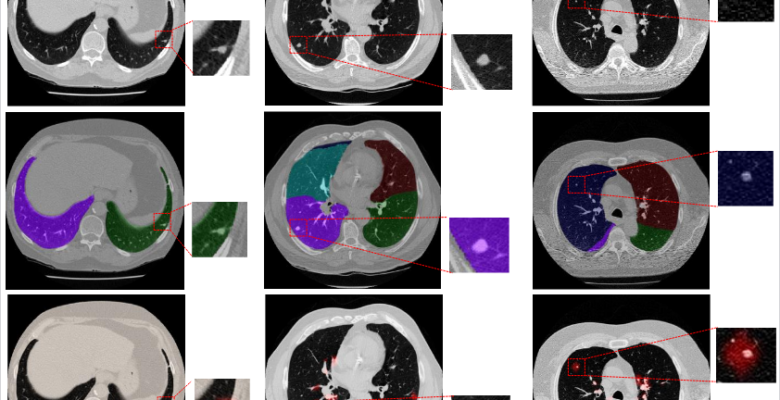

Synthetic datasets hold the potential to serve as cost-effective alternatives to clinical data, potentially aiding in mitigating the biases in clinical data. This paper presents a novel method that utilizes such datasets to train a computer-aided detection (CADe) algorithm. Our proposed approach uses images of a physical anthropomorphic phantom into which manufactured objects representing simplified lesions were inserted, followed by a set of randomized and parametrized augmentations of the data to increase the variability in these datasets. By incorporating these augmentations into the training phase, our proposed method aims to add variability within training datasets of limited size to improve model performance. We apply our proposed method to the false positive reduction stage of a lung nodule CADe system on computed tomography (CT) scans.